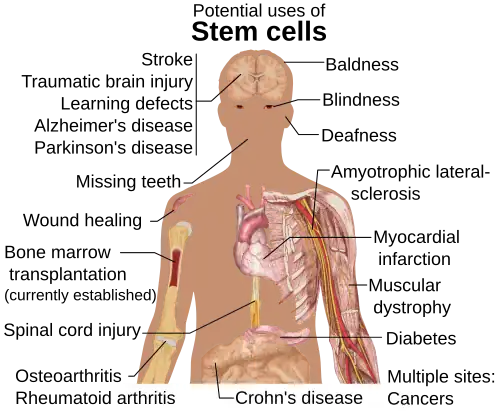

Stem cell therapy is the use of stem cells to treat or prevent a disease or condition. Bone marrow transplant is a form of stem cell therapy that has been used for many years because it has proven to be effective in clinical trials.[95][96] Stem cell implantation may help in strengthening the left-ventricle of the heart, as well as retaining the heart tissue to patients who have suffered from heart attacks in the past.[97]

For over 50 years, hematopoietic stem cell transplantation (HSCT) has been used to treat people with conditions such as leukaemia and lymphoma; this is the only widely practiced form of stem-cell therapy.[95][96][98] As of 2016, the only established therapy using stem cells is hematopoietic stem cell transplantation.[4] This usually takes the form of a bone-marrow transplantation, but the cells can also be derived from umbilical cord blood. Research is underway to develop various sources for stem cells as well as to apply stem-cell treatments for neurodegenerative diseases[99][30]>[100] and conditions such as diabetes and heart disease.

Diseases and conditions where stem cell treatment is being investigated include:

- Diabetes[123]

- Androgenic Alopecia and hair loss[124][125]

- Rheumatoid arthritis[123]

- Parkinson's disease[123]

- Alzheimer's disease[123]

- Respiratory disease[126]

- Osteoarthritis[123]

- Stroke and traumatic brain injury repair[127]

- Learning disability due to congenital disorder[128]

- Spinal cord injury repair[129]

- Heart infarction[130]

- Anti-cancer treatments[127]

- Baldness reversal[131]

- Replace missing teeth[132]

- Repair hearing[133]

- Restore vision[134] and repair damage to the cornea[135]

- Amyotrophic lateral sclerosis[136]

- Crohn's disease[137]

- Wound healing[138]

- Male infertility due to absence of spermatogonial stem cells.[139] In recent studies, scientists have found a way to solve this problem by reprogramming a cell and turning it into a spermatozoon. Other studies have proven the restoration of spermatogenesis by introducing human iPSC cells in mice testicles. This could mean the end of azoospermia.[140]

- Female infertility: oocytes made from embryonic stem cells. Scientists have found the ovarian stem cells, a rare type of cells (0.014%) found in the ovary. They could be used as a treatment not only for infertility, but also for premature ovarian insufficiency (POI).[141] New research posted in Science Direct suggests that ovarian follicles could be triggered to grow in the ovarian environment by using stem cells present in bone marrow. This study was conducted by infusing human bone marrow stem cells into immune-deficient mice to improve fertilization.[142] Another study conducted using mice with damaged ovarian function from chemothearpy found that in vivo therapy with bone marrow stem cells can heal the damaged ovaries.[143] Both of these studies are proof-of-concept and need to be furthered tested, but they have the possibility improve fertility for individuals who have POI from chemothearpy treatment.

- Critical Limb Ischemia[144]